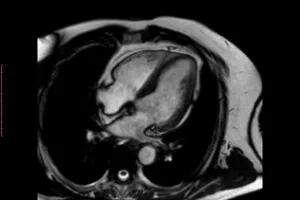

Guía completa sobre la resonancia magnética cardiaca

La resonancia magnética cardiaca es una herramienta de diagnóstico avanzada que ofrece una…